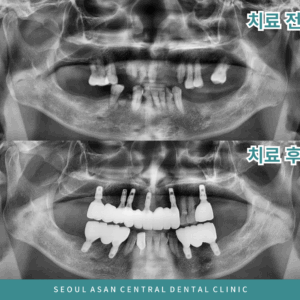

성남치과 임플란트와 틀니 치료 전후 파노라마 사진

성남치과 전체임플란트 치료 전후 파노라마 사진